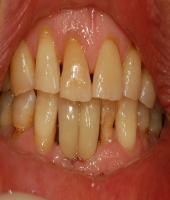

| ● 진료과목 : [심미보철] 돌출치아의 치료

| ● 내용 : 사고로 인한 돌출치아의 치료 |